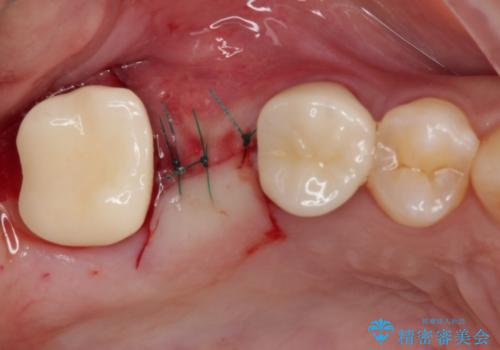

外科処置を回避するためにブリッジ治療を選択されたそうですが、頻繁に脱離するので、欠けた部分のクラウンの作り替えと、欠損部のインプラント治療を行うこととしました。

最後方歯は、クラウンを維持するための高さが不足していたため、インプラント処置の際に歯冠長を延長する手術を併用し、維持力を増すこととしました。

上顎洞までの骨高さが低いケースでしたが、ショートインプラントと骨圧縮機能を持つドリルの使用により、上顎洞底挙上を行うことなく、インプラント治療を行うことができました。